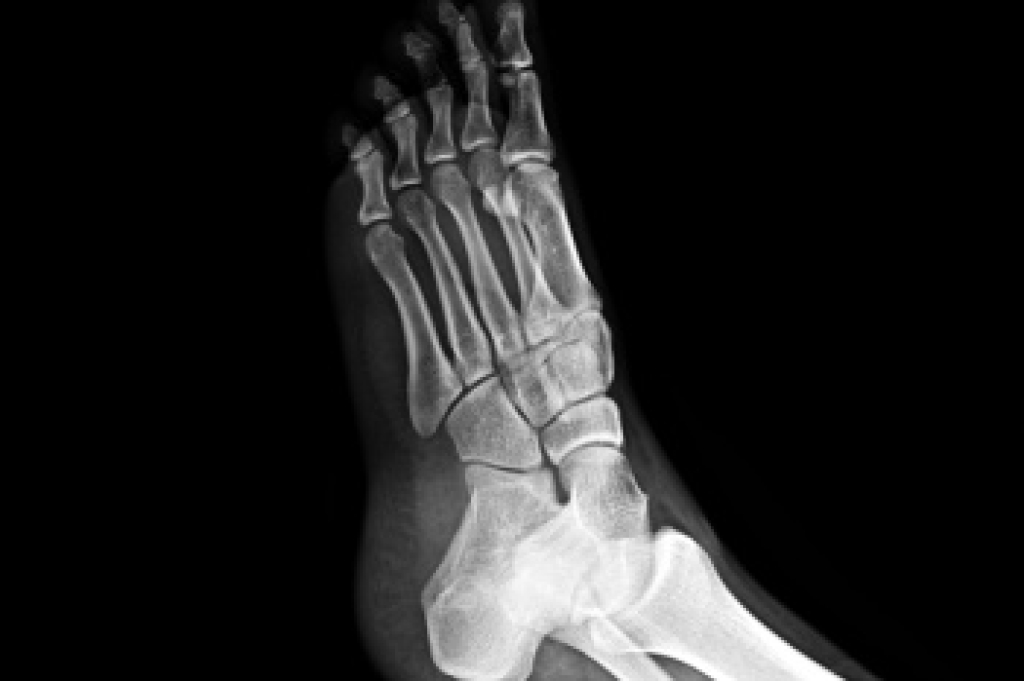

Stress fractures occur in the foot and ankle when muscles in these areas weaken from too much or too little use. The feet and ankles then lose support when walking or running from the impact of the ground. Since there is no protection, the bones receive the full impact of each step. Stress on the feet can cause cracks to form in the bones, thus creating stress fractures.

Pain from the fractures occur in the area of the fractures and can be constant or intermittent. It will often cause sharp or dull pain with swelling and tenderness. Engaging in any kind of activity which involves high impact will aggravate pain.